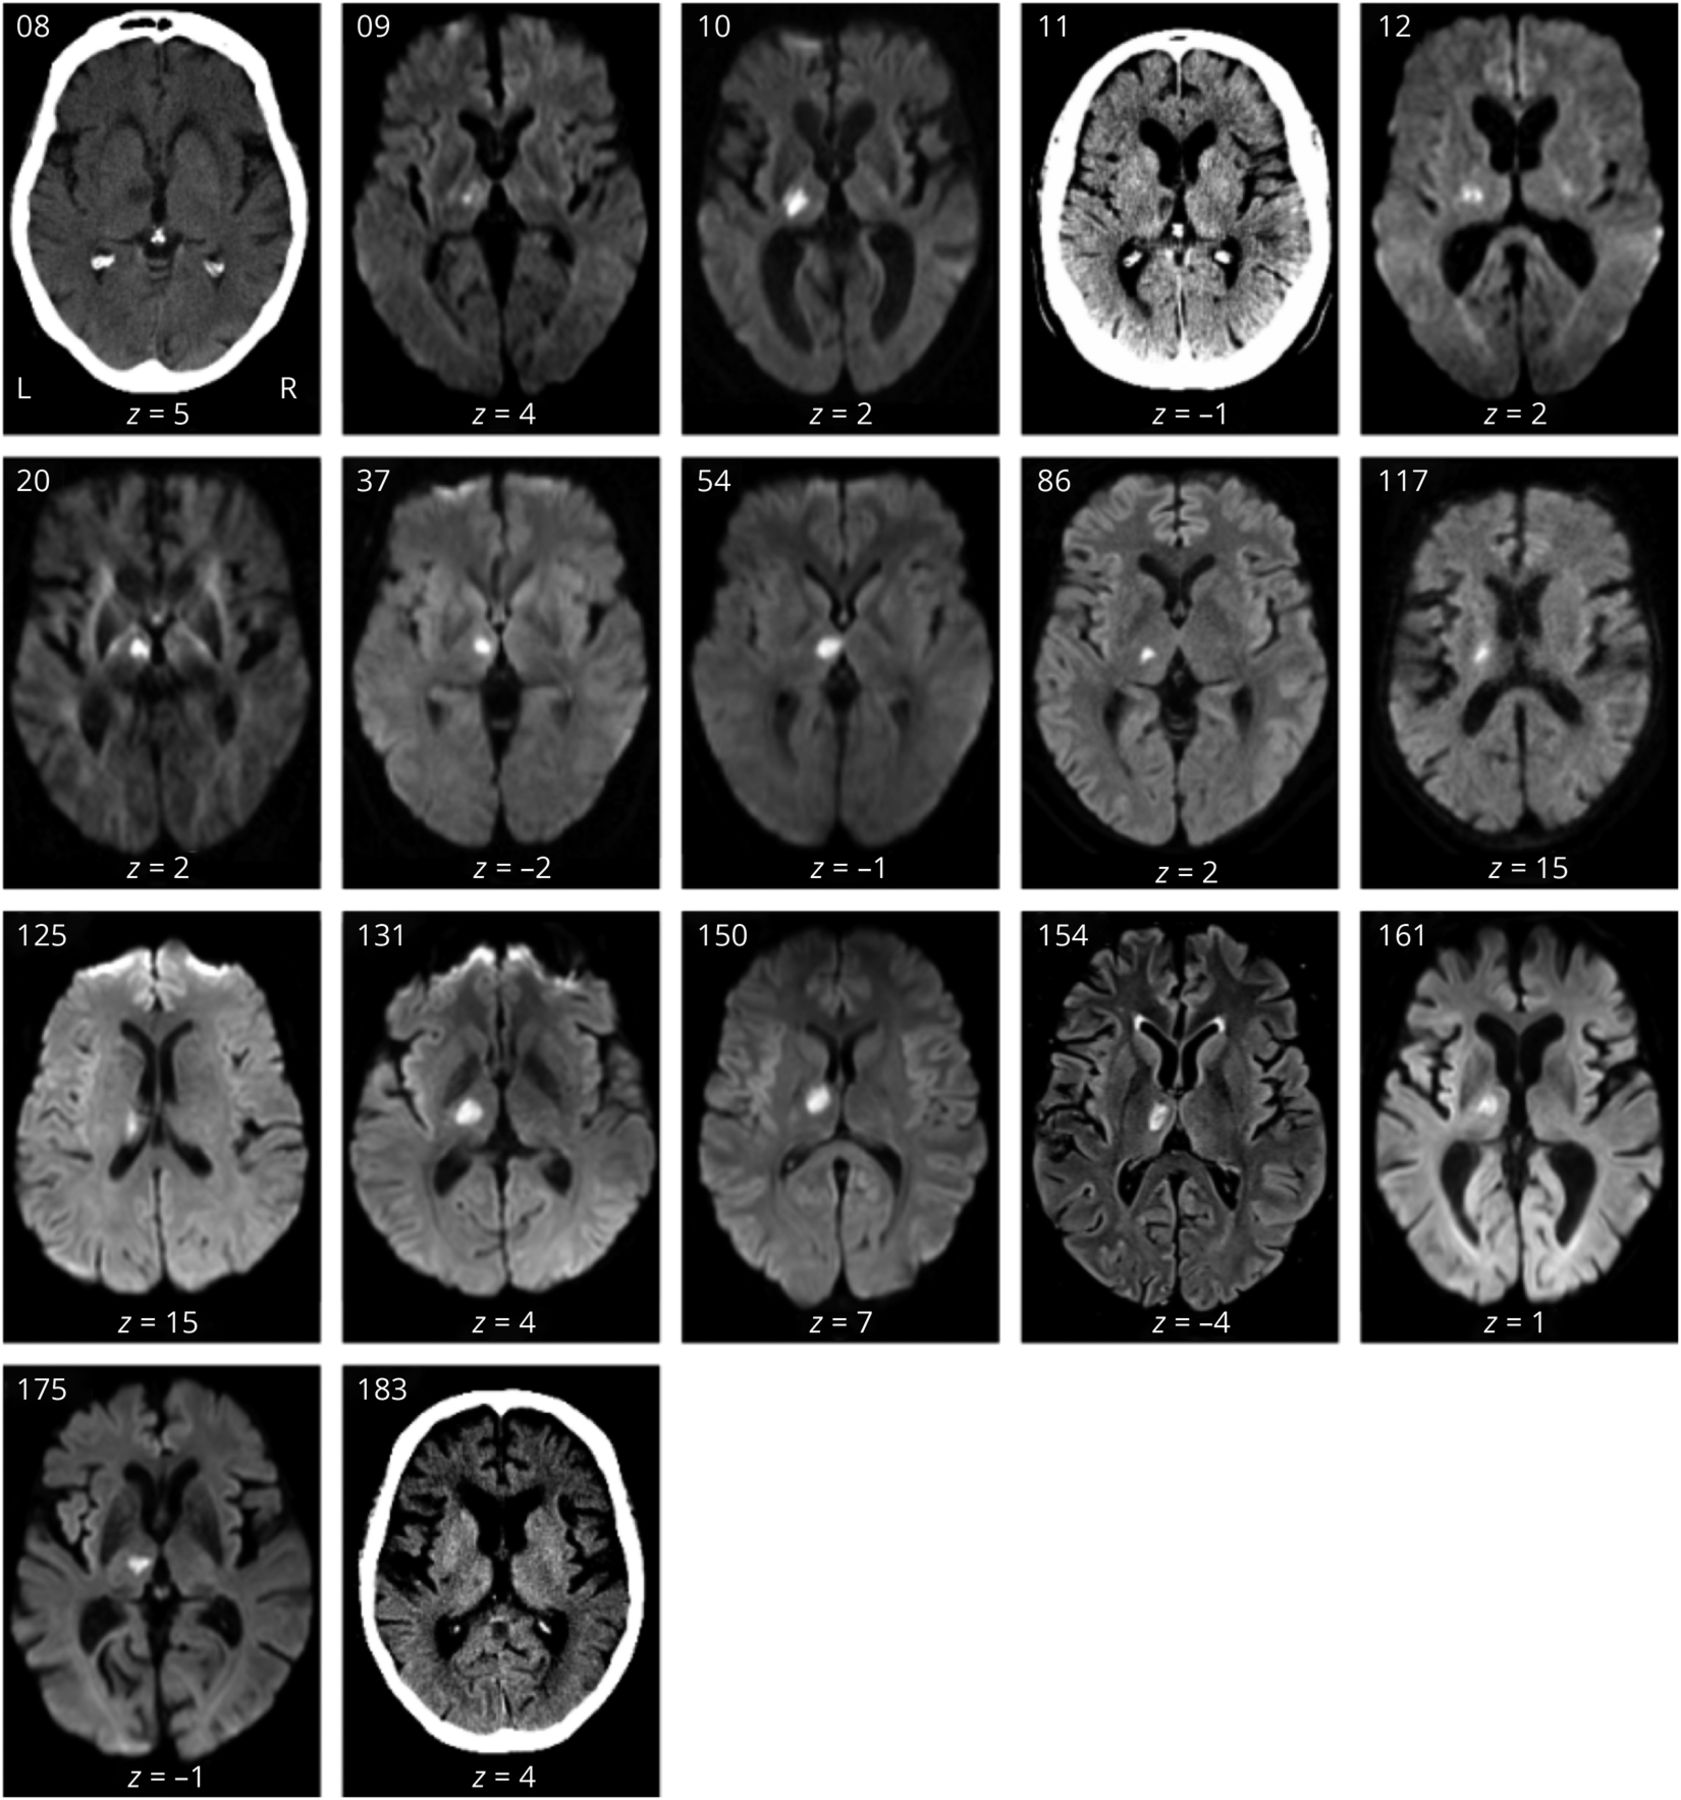

所有病变均分布在后循环区,最大病变重叠于丘脑左腹外侧核(n = 24/101例患者)。图2一个).所有患者中,只有至少10% (n≥10)的体素受影响进行了后续的VLSM分析。因此,两个丘脑的部分(即最外侧、后缘和前缘)不能包括在分析中(图2 b).

(A)病变频率图:MRI叠加101例患者在MNI空间的病变重叠(ch2bet模板分布与MRIcron)。颜色条表示每个体素中病灶重叠的患者数量,热色表示该区域病变患者数量较多。最大病变重叠位于左腹侧核(MNI - 16, - 20,2;N = 24)。(B)在所有患者中,只有至少10% (n≥10)的受影响区域进行了基于体素的病变-症状映射分析。虚线标记丘脑边界。代表性轴向切片在MNI空间中,每个图像下方报告z坐标。蒙特利尔神经学研究所。

本研究中纳入的患者病变分布于两侧丘脑。与其他研究一致,根据外侧丘脑是最常见的病变位置,腹外侧丘脑最常受影响(图2一个)。24,25前内侧和后内侧丘脑核受影响的频率较低,因此不能纳入VLSM分析,尽管先前的病例研究结果确实报告了这些核病变后的丘脑失语症(表1,links.lww.com/WNL/C447).作为主要结果,VLSM分析显示,与构音障碍和运动或感觉障碍患者相比,语言障碍患者左侧背中核更容易受损(图3青色)。后两种表现出与语言障碍在空间上截然不同的损伤-症状关联(图3(红色和绿色),并与先前腹侧和后外侧核参与运动和躯体感觉的证据一致。26虽然与报告左侧背中核累及丘脑失语症的病例研究一致(表1),但我们的研究基于更大样本的体素统计比较提供了额外的经验证据。基于任务的功能磁共振成像也证实了左背中核对语言的贡献,表明其在语义记忆和词汇-语义处理中发挥作用。27,-,29几项功能磁共振成像研究显示,丘脑峰分布的可视化显示左侧靠近中线区域(板内核和背中核)的聚类,特别是在感知挑战性的语言任务中。30.这可能与执行功能和语言功能之间的重叠有关,例如,对语言处理的领域一般执行控制可能会随着任务需求的增加而发挥作用。31,-,33在这种情况下,认知的调节作用一般被归因于背中核。8,34与此一致,一项损伤研究表明,丘脑背中核损伤导致执行功能受损,并提出丘脑皮质网络功能障碍导致这些缺陷。35在接下来的文章中,我们将讨论LNSM结果,特别关注涉及语言和领域通用网络的识别模式。